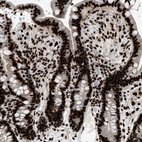

Immunohistochemical staining of human cerebral cortex, gastrointestinal, kidney and lymphoid tissues using Anti-LUC7L3 antibody HPA020017 (A) shows similar protein distribution across tissues to independent antibody HPA018475 (B).